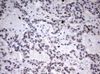

Applications IHC, WB

Recommended Dilution WB 1:2000, IHC 1:150